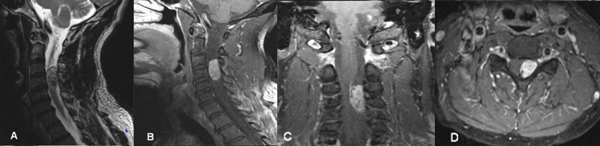

Fig 1. Caso 1. RMN: T2 sagital (A) y T1 con contraste sagital (B) coronal (C) y axial (D) que evidencia lesión nodular intradural extramedular C3-C4 a izquierda, con realce homogéneo post contraste que desplaza y comprime la médula en sentido lateral.